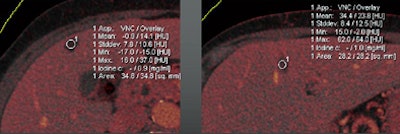

The technique can be used to determine the contrast media uptake of the polyp, as well as the baseline density of the lesion, directly measuring enhancement in HU and measuring the iodine in the lesion in grams per mL.

| Images are of a 65-year-old male patient who underwent a single acquisition at dual-source CTC. Above, a stenosing carcinoma was seen in the proximal sigmoid colon in 3D endoluminal views (left, middle) and 2D view (right). Below, an 18-mm colorectal adenoma was also found in the proximal sigmoid colon, and also appears to be enhancing. Bottom image shows an enhancing liver metastasis in the same patient. Virtual unenhanced (grayscale) images are created by electronically subtracting the contrast media. All images courtesy of Dr. Anno Graser. |

The mean enhancement of adenomas was 55 ± 27 HU.

The mean enhancement of hyperplastic lesions was 13 ± 10 HU.